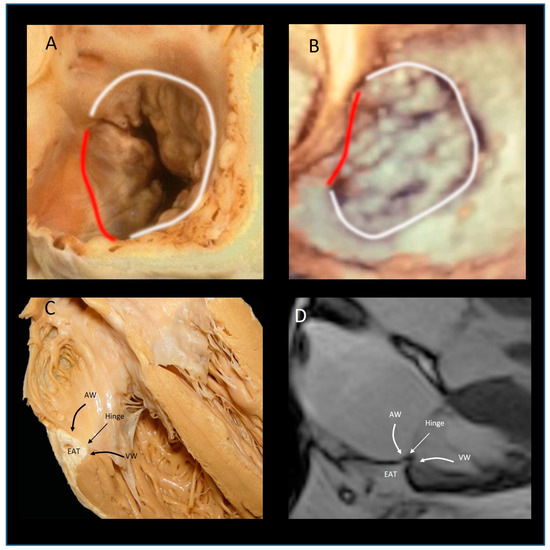

The “Mural” Annulus

4. The “Septal” Annulus

5. Physiological and Physiopathologic Consequences of the Annular Structure